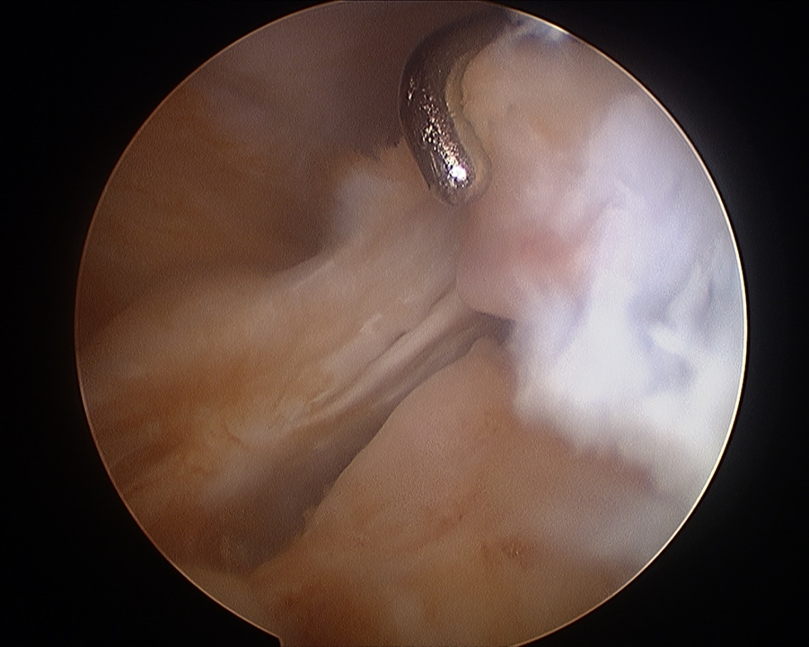

Arthroscopy

Have to look either posteromedial or posterolateral to identify